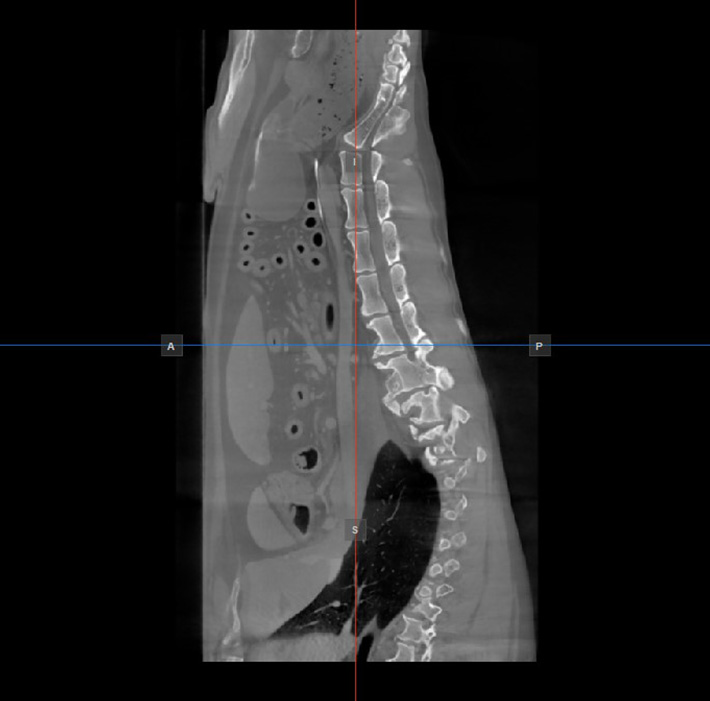

Az aktív nézetablakban nem látható másik két kép síkjának helyzetét és metszését két függőleges és vízszintes vonal jelzi, amelyeket szeletelőknek nevezünk. Minden szeletelő végpontját egy betű jelöli, amely a 3D térfogat megfelelő irányának/oldalának felel meg az RAS koordinátarendszer alapján.

Az elérhető hat oldalból csak négy van jelölve minden 2D nézetablakon. A címkék és a hozzájuk tartozó oldalak a következők:

Beteg jobb oldala (R), a test jobb oldalát jelöli

Beteg bal oldala (L), a test bal oldalát jelöli

Elülső (A), a test elülső oldalát jelöli

Hátsó (P), a test hátsó oldalát jelöli

Felső (S), a test felső oldalát jelöli

Alsó (I), a test alsó oldalát jelöli